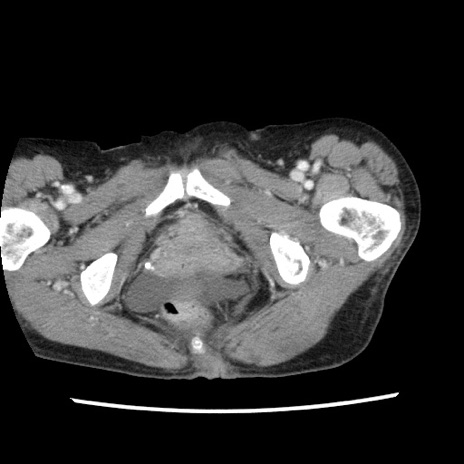

症例1(横断像)

【症例】80歳代女性

【主訴】腹痛

【現病歴】8時間前から腹痛あり来院。

【既往歴】糖尿病、脂質異常症、子宮体癌にて子宮全摘術

【身体所見】意識清明・会話良好だが腹痛で苦悶様、全腹部にわたって反跳痛と圧痛あり

【データ】WBC 13600、CRP 0.14、LDH 224、CK 90